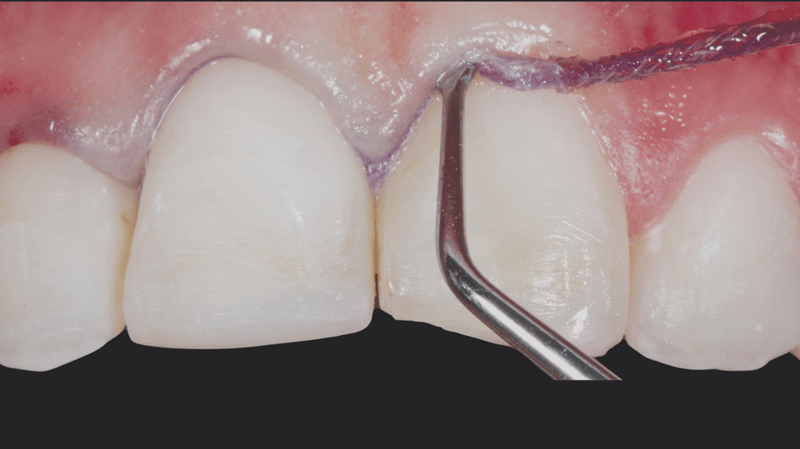

- Gingival Sulcus Preparation: Ultrapak™ knitted cord Size #0 was packed into the gingival sulcus to prepare for etching.

- Etching Uncut Enamel: A 30-second etch was performed using Ultra-Etch 35% phosphoric acid on the uncut enamel.

- Adhesive Application and Thinning: Peak Universal Bond adhesive was applied and thinned with air and suction.

- Cementation: The veneers were cemented using PermaShade™ LC luting resin in the Translucent shade (not available in Europe).